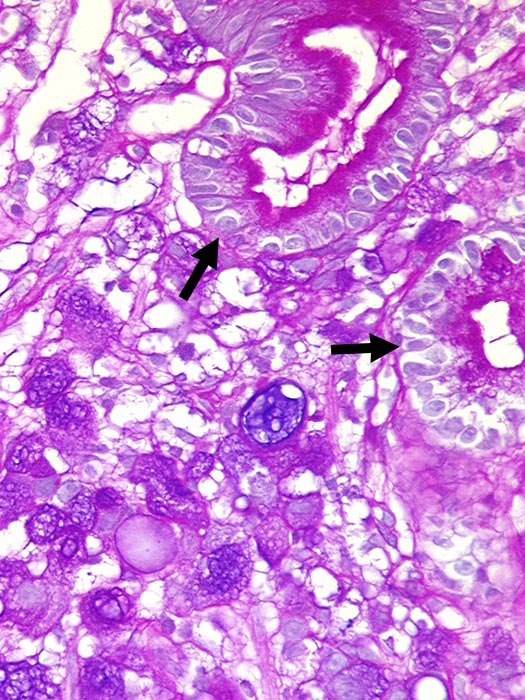

PathoPic ID 1338 - Adenokarzinom diffuser Typ nach Lauren : Siegelringzellen

Adenokarzinom diffuser Typ nach Lauren : Siegelringzellen

Intaktes

Magenepithel. Die Tumorzellen im Stroma enthalten reichlich

alcianblauen Schleim im Zytoplasma.